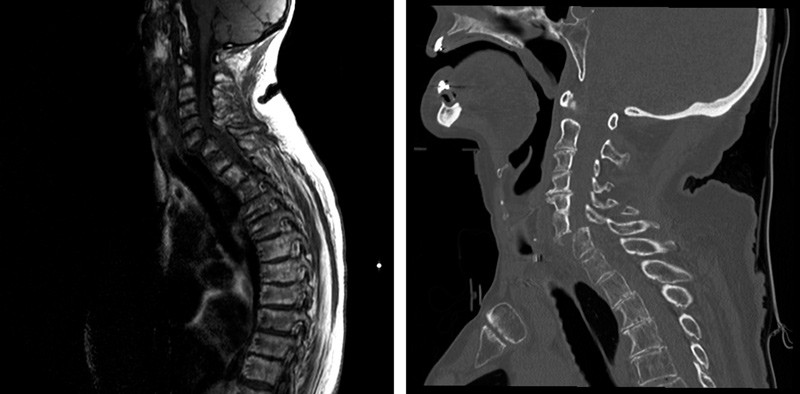

EKG viste rask atrieflimmer. Hun ble undersøkt med CT av hodet, blodprøver, urinstiks, blodgass, rytmeovervåkning og EEG for mistanke om infeksjon, arytmi eller epileptisk anfall. CT av hodet viste residiv av et tidligere operert meningeom frontalt på høyre side samt et nytt meningeom parietalt på venstre side. EEG tatt to dager etter innleggelsen viste ikke epileptiform aktivitet. Nevrologen som så spasmene under EEG-registreringen overveide dystone anfall. Imidlertid hadde de hyppige høyresidige rykningene samme fleksjonsmønster som ved invertert plantarrefleks, vist ved Babinskis tegn (video). Rykningene kom stadig spontant, av og til også på venstre side, og kunne utløses ved lett berøring av huden. Nevrologen fikk derfor mistanke om myelopati. Ved ny nevrologisk undersøkelse hadde pasienten redusert kraft for håndtrykk bilateralt og var spastisk i underekstremitetene. Akutt MR viste cervikal myelopati (bildet til venstre), og CT av nakken viste luksasjonsfraktur i nivå C6/C7 med avklemming av ryggmargen (bildet til høyre). Ved overflytting til nevrokirurgisk avdeling var hun tetraparetisk, men hadde bevart sensibilitet. Hun ble øyeblikkelig operert med bakre fiksasjon og etter to dager reoperert med fremre fiksasjon i nivå C6/C7. Rykningene i føttene forsvant, men hun hadde vedvarende paralyse distalt i bein og armer og grad 2 – 4/5 pareser proksimalt. Kvinnen døde kort tid etter.